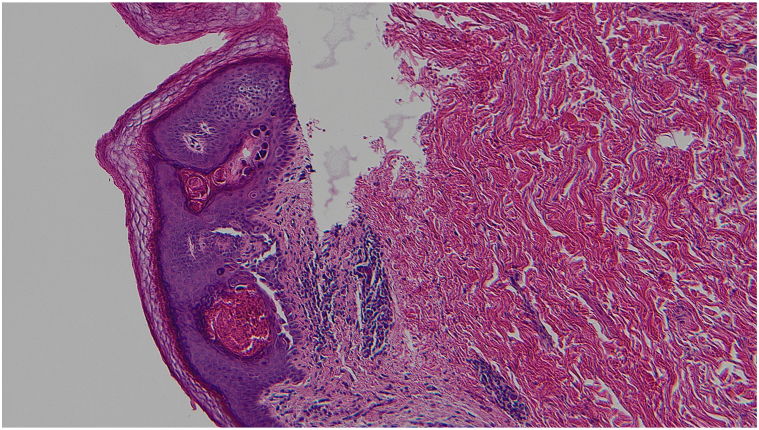

The initial histopathologic examination was done by a breast pathologist who only described a benign epidermoid cyst. The patient was referred to the dermatology clinic for management of the residual lesion. As the clinical presentation did not correlate with the diagnosis of an epidermal cyst, the slides were reviewed by a dermatopathologist with a corrected diagnostic of acantholytic dyskeratosis. With deeper levels cut in the biopsies’ cell blocks, the histopathologic examination demonstrated suprabasilar clefts in the epidermis with discohesive rounded keratinocytes (acantholysis). There was also dyskeratosis with 2 types of dyskeratotic cells, one type consisting of hypereosinophilic keratinocytes with pyknotic nuclei (corps grains) and the other type consisting of acantholytic keratinocytes with a larger nucleus and a perinuclear halo (corps ronds) (Figs 3 and 4). The skin appendages were spared by the acantholytic dyskeratosis.

Fig 3.

Hematoxylin and eosin-stained slide showing acantholytic dyskeratosis with suprabasilar clefts with corps ronds and corps grains. (Hematoxylin-eosin stain; original magnification: ×100.)